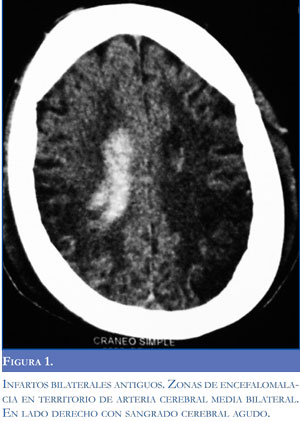

Una arteriografía realizada durante la primera semana de evolución mostró estenosis de la carótida izquierda con adelgazamiento distal de la vascula-tura cerebral con neoformación y colateralización de circulación externa con la interna conformando un patrón típico de síndrome moyamoya (Figuras 3, 4, 5 y 6). El control imagenológico hacia los 15 días de hospitalización evidenció una disminución del 50% en el volumen del sangrado intraventricular. La paciente logró llegar a un alertamiento espontáneo sin contenido de la conciencia ni respuesta al llamado. A los 45 días de evolución logra salir de UCIN con traqueostomía percutánea y nutrición por gastrostomía.

El termino moyamoya fue introducido por Suzuki y Takaku en 1957 por el aspecto angiográ-fico de la circulación colateral cerebral en humo de cigarrillo o fumarola (en japonés "moyamoya"). En esta entidad existe una esteno-oclusión de múltiples vasos intracraneales con aparición de colaterales del polígono de Willis, leptomeningeas o con formación de aneurismas u otras malformaciones arteriovenosas. Cuando existen colaterales entre circulación anterior y posterior o entre la circulación intracraneana y la extracraneana existe mayor riesgo de hemorragia intracraneana. En la enfermedad de moyamoya existe predisposición genética, en cambio, en aquellos pacientes sin la enfermedad pero con el patrón angiográfico típico existe una enfermedad de base (síndrome de moyamoya) que los predispone a desarrollar el daño vascular, como la ateroesclero-sis en ancianos, la neurofibromatosis, la esclerosis tuberosa, la tuberculosis, el síndrome de Down y la enfermedad de células falciformes (5-6). Dobson describió 44 pacientes con enfermedad de células falciformes y demostró que aquellos con síndrome o patrón angiográfico de moyamoya tuvieron más riesgo de eventos cerebrovasculares recurrentes (7).